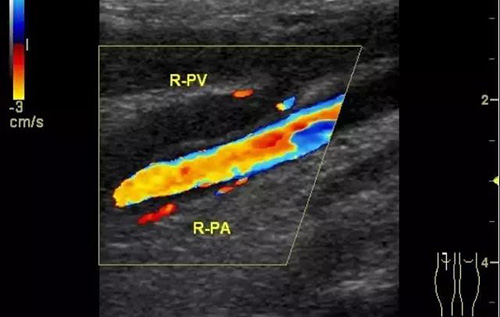

下肢深靜脈血栓形成后綜合征的診斷主要依靠靜脈造影和彩色超聲多普勒,而彩超機具有無創、重復性好、準確率高的優點,逐漸成為診斷此病的首選。

彩色普勒超聲診斷儀,線陣探頭,頻率7.5~10MHz。受檢查者先取仰臥位,患肢髖關節略外旋,大腿輕度外展且膝關節略曲,使整個下肢呈松弛狀態。自上而下順序檢查髂外、股總、股淺、股深及大隱靜脈;之后取俯臥位,檢查靜脈及小腿靜脈。以縱切和橫切顯示血管,灰階超聲主要觀察血管內徑、管壁結構及血栓情況,CDFI主要觀察管腔內有無血流顯示、充盈缺損及血液返流情況,必要時擠壓小腿腓腸肌以利血流顯示。

彩超診斷下肢深靜脈血栓形成后綜合征具有無創、實時、動態、重復性好、準確率高的特點,且能充分了解血管內外的解剖學改變,觀察靜脈管壁、血流充盈、靜脈瓣返流程度以及側支循環是否建立和血栓的溶液情況,可直觀地觀察到血流動力學改變,所以具有很高的使用價值。通過對治療前后聲像圖的對比,可以提示臨床的治療效果,對于臨床治療具有很大的指導作用。